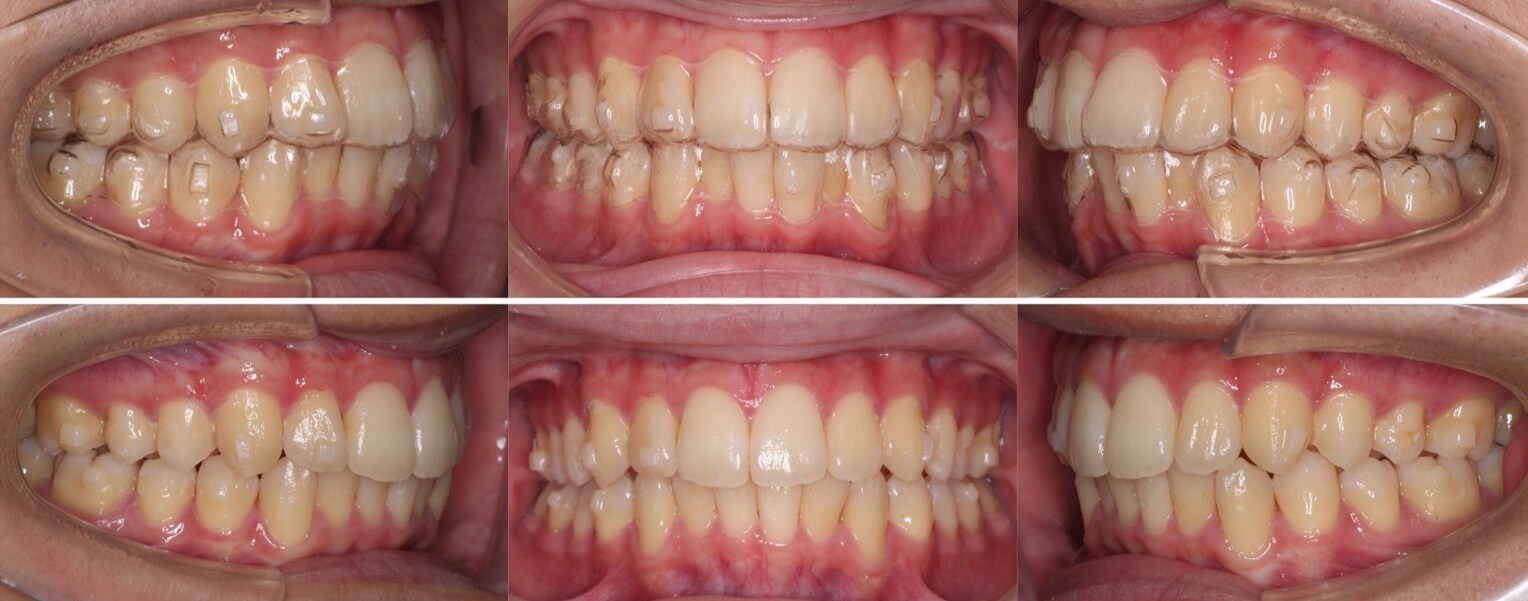

高校生女性・中程度叢生・マウスピース型装置

左側の片側のみに八重歯があり、上下の正中線が不一致となっている症例です。前歯のかみ合わせも上下がしっかりと当たるようになり健康な歯並びになりました。

<症例概要> 難易度★★★☆☆

主訴:八重歯

年齢・性別:高校生女性

住まい:千葉八千代市

症状:叢生・正中線の不一致

治療方針:上顎後方移動・IPR

治療装置:マウスピース型矯正装置(アライナー装置)

治療期間:1年7か月

アライナー枚数:49+16+15ステージ

リテーナー:上下+クリアタイプ

治療費用:990,000(税込)

代表的副作用:痛み・治療後の後戻り・歯根吸収・歯髄壊死・歯肉退縮

顎間ゴムを使用して、左上にスペースを作り八重歯を下ろしてきました。